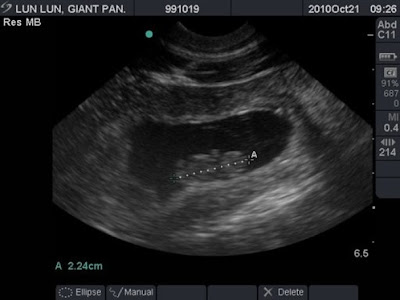

Thaipanda+: Zoo Atlanta's 13-year-old Giant Panda Lun Lun Is Pregnant

Thaipanda+: Zoo Atlanta's 13-year-old giant panda Lun Lun is pregnant thaipandaplus.blogspot.com

Zoo Atlanta's 13-year-old Giant Panda Lun Lun Is Pregnant With Her

Zoo Atlanta's 13-year-old giant panda Lun Lun is pregnant with her animalfwd.blogspot.com

panda giant year old zoo lun atlanta pregnant cub third her yang

Zoo Atlanta's 13-year-old giant panda Lun Lun is pregnant with her pandafwd.blogspot.com

panda lun giant pregnant atlanta zoo year old ultrasound ap cub third her yang